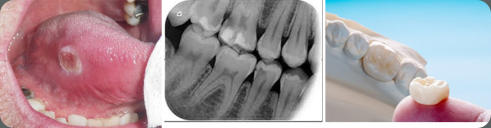

Cirugía

Endodoncia

Patología Oral

Coronas